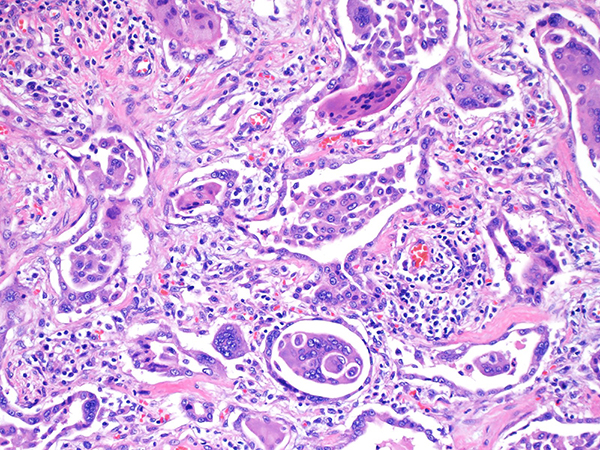

Clinically, patients present with cough and dyspnea and diffuse lung infiltrates on imaging. Histologically, hard metal pneumoconiosis (HMP) is characterized by marked interstitial fibrosis and cellular interstitial infiltrates that are more centered around bronchioles (Figs. 2 and 3) with a predominance of alveolar space giant cells. Therefore, HMP is also known as giant cell interstitial pneumonia (GIP). GIP is almost always associated with hard metal pneumoconiosis, however, rare cases with no history of hard metal exposure have been described. In cases with no exposure history, GIP should be the diagnosis rather than HMP. The key finding in HMP/GIP is the presence of prominent collections of intra-alveolar macrophages and large multinucleated giant cells (Fig. 4), some showing emperipolesis highlighted by the arrow (Fig. 5). Microanalytic studies can identify tungsten in the tissue, but cobalt which is considered the main etiologic agent is water soluble and usually not present after processing. Collagenous nodules with pigmented macrophages and polarizable silica are seen in mixed dust fibrosis and not HMP.

The differential diagnosis includes respiratory bronchiolitis/desquamative interstitial pneumonia, however, the presence of large multinucleated giant cells within the alveolar spaces with focal cannibalism as well as alveolar septal chronic inflammation and/or fibrosis should exclude these diagnoses. Clinical history of hard metal exposure would be helpful in arriving at the correct diagnosis.